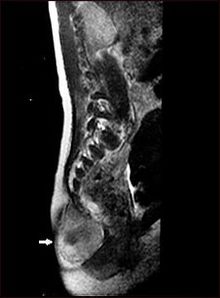

ورم مسخي أو تيراتوما إنگليزية: Teratomaهو نوع من الأورام التي قد تحدث تشوهات لدى الجنين أو الشخص المصاب به. لا يتم التوصل إلى تشخيص نهائي للورم قبل تحليل عينة من الأنسجة الورم.

ينشأ الورم المسخي من طبقات التبرعم الثلاث، ونادرا ما يحدث خلاف ذلك. ولذلك قد نجد جميع أنسجة الجسم موجودة بداخل الورم، مثل الشعر والأسنان والعظم والغضاريف.

في الجنين يكتشف المرض عن طريق الآشعة التلفزيونية ، أما في مرحلة حديث الولادة فتشتكى الأم من " جسم غريب " متضخم ينشأ من جسم المولود .. وللورم أماكن متعددة الظهور .. فقد ينشأ الورم من مؤخرة الطفل أو قدميه أو رأسه وقد يبلغ حجما كبيرا جدا ، ويتم فحص هذا الجزء بالآشعة وبأخذ نسيج من الورم